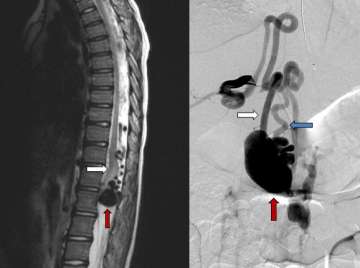

Figure 2. Type IV Pial Spinal Arteriovenous Fistula – sagittal or side view of a T2 MRI of the spine (left) showing a massively enlarged spinal vein (red arrow) compressing the spinal cord (white arrow).

Pial Spinal Arteriovenous Fistulas (Type IV)

- Pial spinal AFVs are a direct connection between an artery and a vein on the surface of the spinal cord. These lesions are very rare and come to attention for various reasons, such as when the vein has become enlarged due to high pressure from the artery and this structure begins to compress the spinal cord (Figure 2).